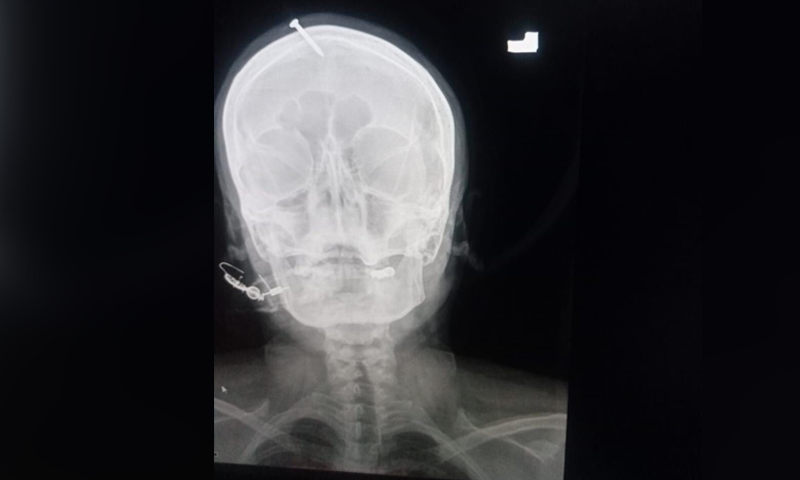

text_fieldsPeshawar: A pregnant woman in Pakistan approached a hospital here with a nail hammered into her head on Wednesday. She said that a faith healer did it to her, promising that the nail act would guarantee her giving birth to a boy, Agence France-Presse (AFP) reported, citing a doctor here.

The woman arrived at the hospital in the northwestern city of Peshawar after trying to extract the nail herself with pliers, doctor Haider Khan told AFP. The woman was under severe pain but was conscious, he said. Khan removed the nail from her head.

According to the doctor, the woman was also a mother to three daughters and was pregnant again with another girl. He added that the nail slightly missed her brain though pierced the top of her forehead. A hammer or a heavy object is used to hammer it in.